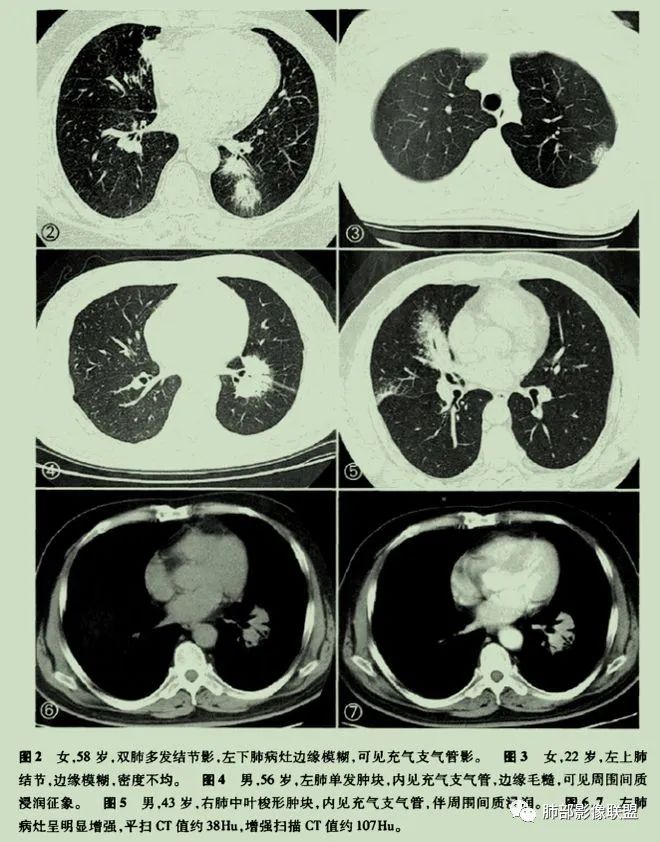

肺淋巴瘤的影像学表现

原发性肺淋巴瘤是一种影响肺部的单克隆淋巴样增生,患者在最初诊断后至少 3个月内没有可检测到的胸外淋巴瘤。原发性肺淋巴瘤很少见,占所有原发性肺肿瘤的 0.5%。原发性肺部受累的淋巴组织增生性疾病包括黏膜相关淋巴组织起源的结外边缘区淋巴瘤(MALT)、弥漫性大 B 细胞淋巴瘤(DLBCL)和淋巴瘤样肉芽肿(LYG)。MALT淋巴瘤是一种低级别B淋巴细胞淋巴瘤,由具有局灶性浆细胞样特征的单调小淋巴细胞组成。它们由沿远端支气管和细支气管分布的上皮下淋巴滤泡组成。肿瘤可能有许多关联,其中包括:干燥综合征、异常丙种球蛋白血症、淀粉样蛋白沉积、胶原血管病、幽门螺杆菌感染和艾滋病等。其影像学表现复杂多变,通常表现为孤立的、界限清楚的软组织肿块。不太常见的成像特征包括:多个单侧或双侧结节沿支气管血管束和小叶间隔弥漫性浸润、广泛的肺叶浸润、模拟实变(肺炎)、伴有空气支气管征或磨玻璃样改变。这些由外淋巴结节、间隔和支气管血管周围增厚组成的间质模式看起来与癌性淋巴管炎或结节病所见的相同。

中央淋巴道分布(支气管血管束分布)外周淋巴道分布(小叶间隔和胸膜下分布)

肺淋巴瘤表现多种多样。可表现为多发小结节!

有时表现为渗出性病变、肿块!

或实变+结节!

抗感染无好转的空气支气管征要警惕肺淋巴瘤。

或表现为网格状阴影,少数不典型的患者表现为弥漫性磨玻璃阴影。

有时候诊断不容易,可酷似肺炎!

或酷似肺癌!

注意:

①低度恶性的病变可以浸润肺间质但不破坏支气管结构。

②恶性程度较高、生长较快的病变可出现中心液化坏死、空洞。

③除非合并感染或曾经治疗,病变一般不会出现钙化。

④20%的患者出现胸腔积液、肺门或纵隔淋巴结肿大。

⑤少见表现为间质性病变及肺不张等。

⑥CT引导下肺穿刺和支气管镜检查确诊率低。支气管镜检查及CT引导下经皮肺活检对该病诊断有一定提示作用,确诊常需要外科肺活检。

⑦内乳淋巴结肿大 (下图) 高度提示肺淋巴瘤。假如患者没有乳腺癌,内乳淋巴结肿大高度提示淋巴瘤,其他疾病引起内乳淋巴结肿大不常见,结节病、肝癌、恶性胸腺瘤偶有报道。